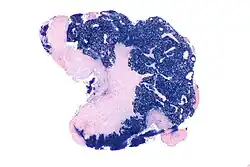

| Micrograph showing a nasopharyngeal carcinoma positive for Epstein-Barr virus-encoded small RNAs (EBER). | |

Nasopharyngeal carcinoma, also known as nasopharyngeal cancer, is classified as a malignant neoplasm, or cancer, arising from the mucosal epithelium of the nasopharynx, most often within the lateral nasopharyngeal recess or fossa of Rosenmüller (a recess behind the entrance of the eustachian tube opening). The World Health Organization classifies nasopharyngeal carcinoma in three types, in order of frequency: Non-keratinizing squamous cell carcinoma; keratinizing squamous cell carcinoma; and basaloid squamous cell carcinoma.[15] The tumor must show evidence of squamous differentiation; with the non-keratinizing type (also known as lymphoepithelioma), the tumor is most strongly associated with Epstein–Barr virus infection of the cancerous cells.[16]

-

Undifferentiated nasopharyngeal carcinoma—low power -

Undifferentiated nasopharyngeal carcinoma—med. power -

Undifferentiated nasopharyngeal carcinoma—high power -

Undifferentiated nasopharyngeal carcinoma—high power